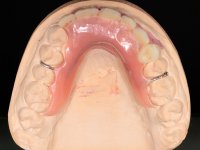

O paciente foi observado conjuntamente e a dúvida que surgiu de imediato foi se seria possível com a regeneração óssea a efectuar poder ser reabilitada naturalmente a zona das papilas interdentárias. Nesse sentido foi feito um enceramento de diagnóstico que contemplaria as duas hipóteses, utilizando ou não a cerâmica gengival. A confecção desse enceramento foi fundamental para expor ao paciente a dificuldade da reabilitação. O wax-up deu origem a um mock-up que foi aprovado pelo paciente e que simultaneamente serviu de guia imagiológica. O caso foi planificado cirurgicamente e realizada uma guia cirúrgica com que foram colocados os implantes. Após 10 semanas foi feita a 1ª impressão para confecção da ponte provisória. Foram criados os primeiros perfis de emergência na gengiva artificial e foi digitalizado o modelo. Por processo de CAD-CAM foi confeccionada uma ponte provisória aparafusada baseada no enceramento de diagnóstico. A ponte trabalhou durante 8 semanas os tecidos moles que foram fielmente copiados numa impressão com técnica de moldeira aberta. Os transferes foram individualizados com resina composta para copiarem fielmente os perfis de emergência criados pela ponte provisória. Confeccionado o modelo de trabalho definitivo, foi realizada uma infra-estrutura em zircónio seguindo a orientação do enceramento de diagnóstico. O assentamento da infra-estrutura foi testado em boca e simultaneamente foi novamente impressionados os tecidos moles com um silicone fluido. Nessa consulta foi feito o levantamento da cor. Os dentes 13 e 23 apresentavam uma saturação anormalmente forte que resolvemos não valorizar, optando por privilegiar a relação com o sector antero-inferior. Foi realizada uma nova gengiva artificial com a impressão que acompanhou a impressão de arrasto com a infra-estrutura. Após a colocação da cerâmica na infra-estrutura foram coladas as meso-estruturas. O trabalho final foi aparafusado lentamente permitindo a adaptação dos tecidos moles.